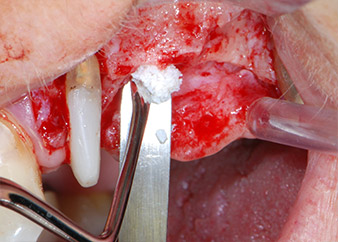

Преди поставянето на импланта, инфектираната тъкан е отстранена от алвеоларната кост в имплантното ложе и около зъба-абатмънт с накрайник, проектиран за оформяне на костта и събиране на костни блокове (Piezomed, накрайник B5) (Фиг. 6 и 7).